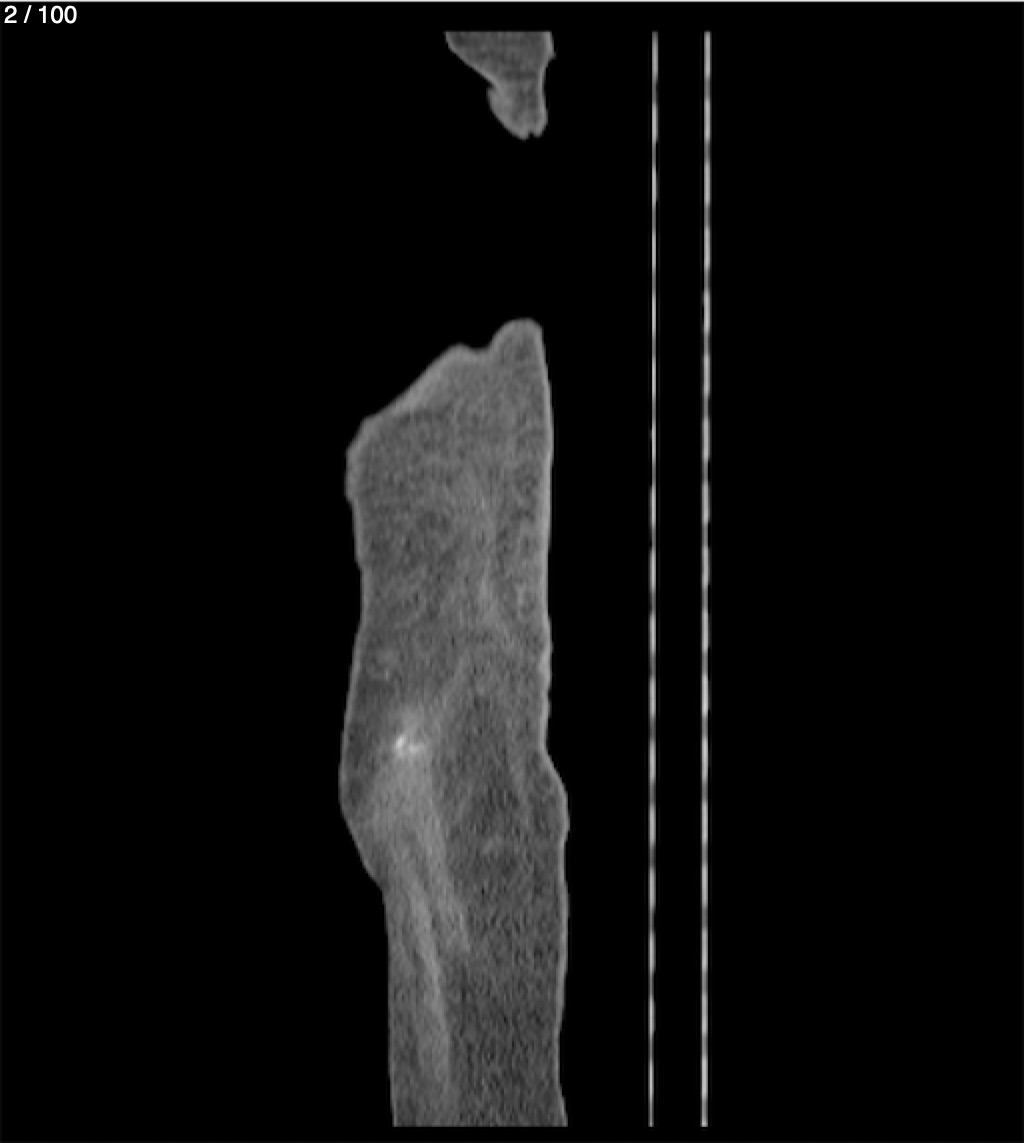

Hilda Geronimo Mendez 60A - T.C Abdomen Simple